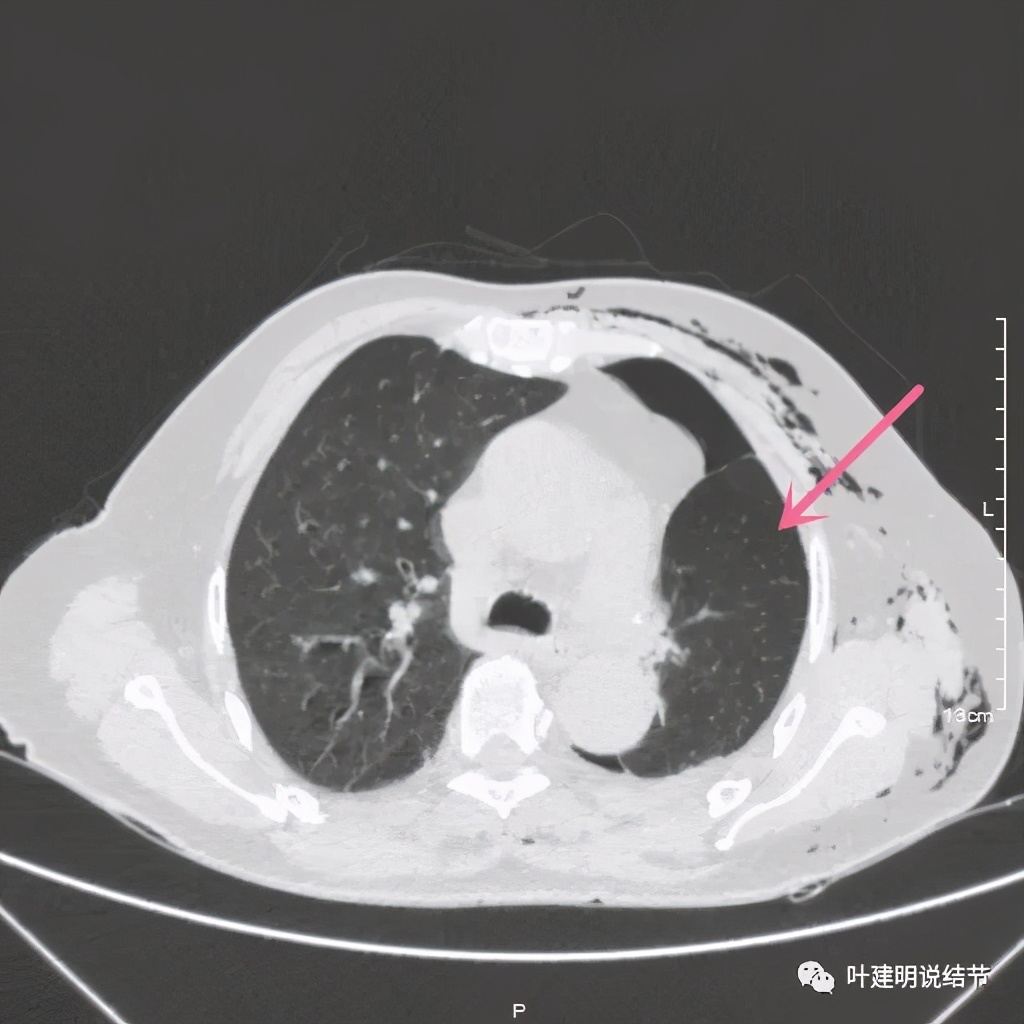

术后第二天患者乏力纳差,起不了床!而且CRP也大于100,我们的神经又紧张起来,怕支气管胸膜瘘,怕感染、怕有并发症发生。还好化验后是低钾,予以补充钾与镁2天后胃纳与精神均有明显改善,我们再加用静脉高营养支持治疗,补充白蛋白,情况逐渐好转。我们也于术后第4天查了CT,发现如下:

下叶膨胀良好

下叶膨胀良好,上叶残腔不大